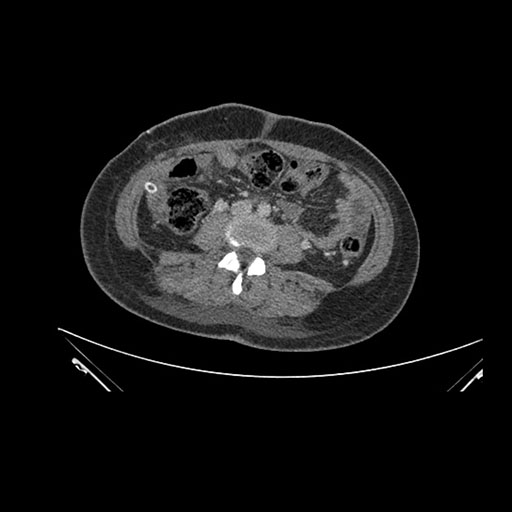

Imaging Analysis

Look through the patient's CT scan to identify any areas of concern for the necessary procedure.

Axial Arterial